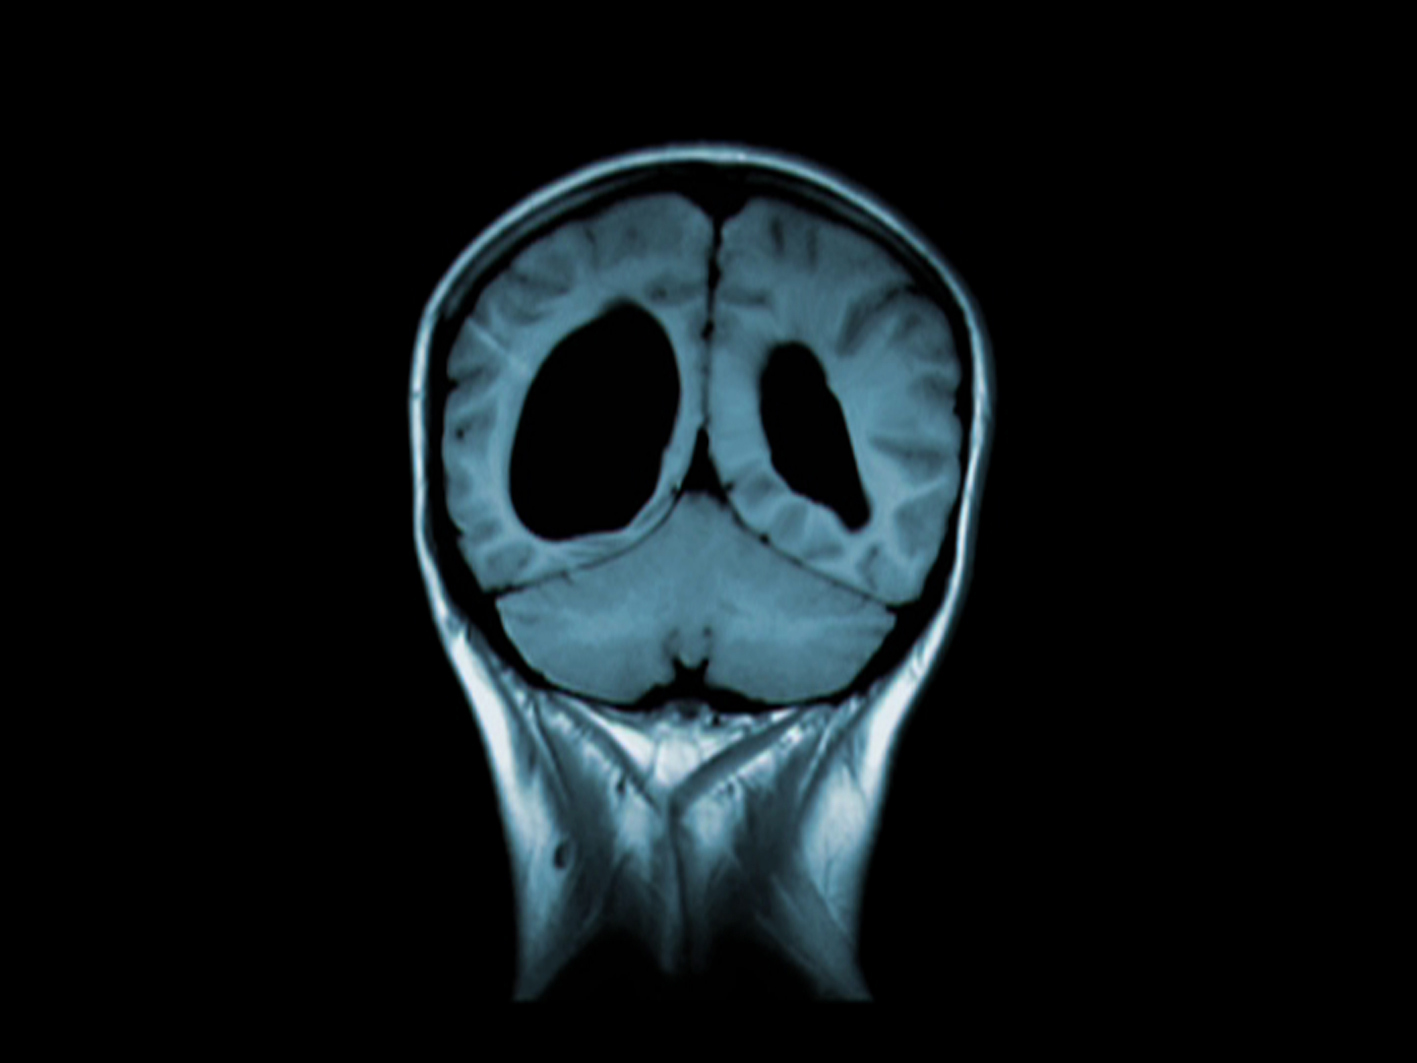

L'idée de Disconnect provient d'un IRM effectué sur le cerveau de jumeaux identiques. L'un des jumeaux est schizophrène. Les ventricules atrophiés de son cerveau, visibles sur la radio sont plus marqués que sur ceux de son frère. Ali M. Demirel a recupéré d'autres images d'IRM effectués sur des schizophrènes.